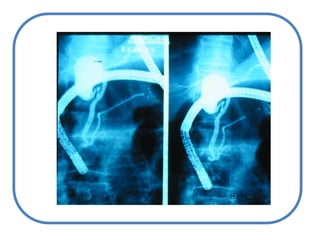

ColestasisIntrahepáticaExtra hepáticaAlteración en el transportadorVías Intra hepáticasHacia el intestinoVías extra hepáticas – pre vesicularesccVesiculares

Anatómica ICTERICIAETIOLOGÍA:CAUSAS POSHEPATICASCAUSAS PREHEPATICASColedocolitiasisAnemia hemolíticaCAUSAS HEPÁTICASCirrosis hepática

Litiasis y estenosis de víasbiliares